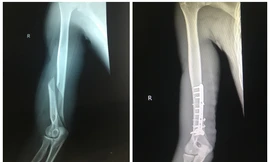

Sau khi đọ sức cùng bạn thông qua trò vật tay, nam thanh nhiên ở Quảng Yên, Quảng Ninh phải vào viện cấp cứu. Xương cánh tay bị gãy vặn xoắn một đoạn khoảng 8cm.